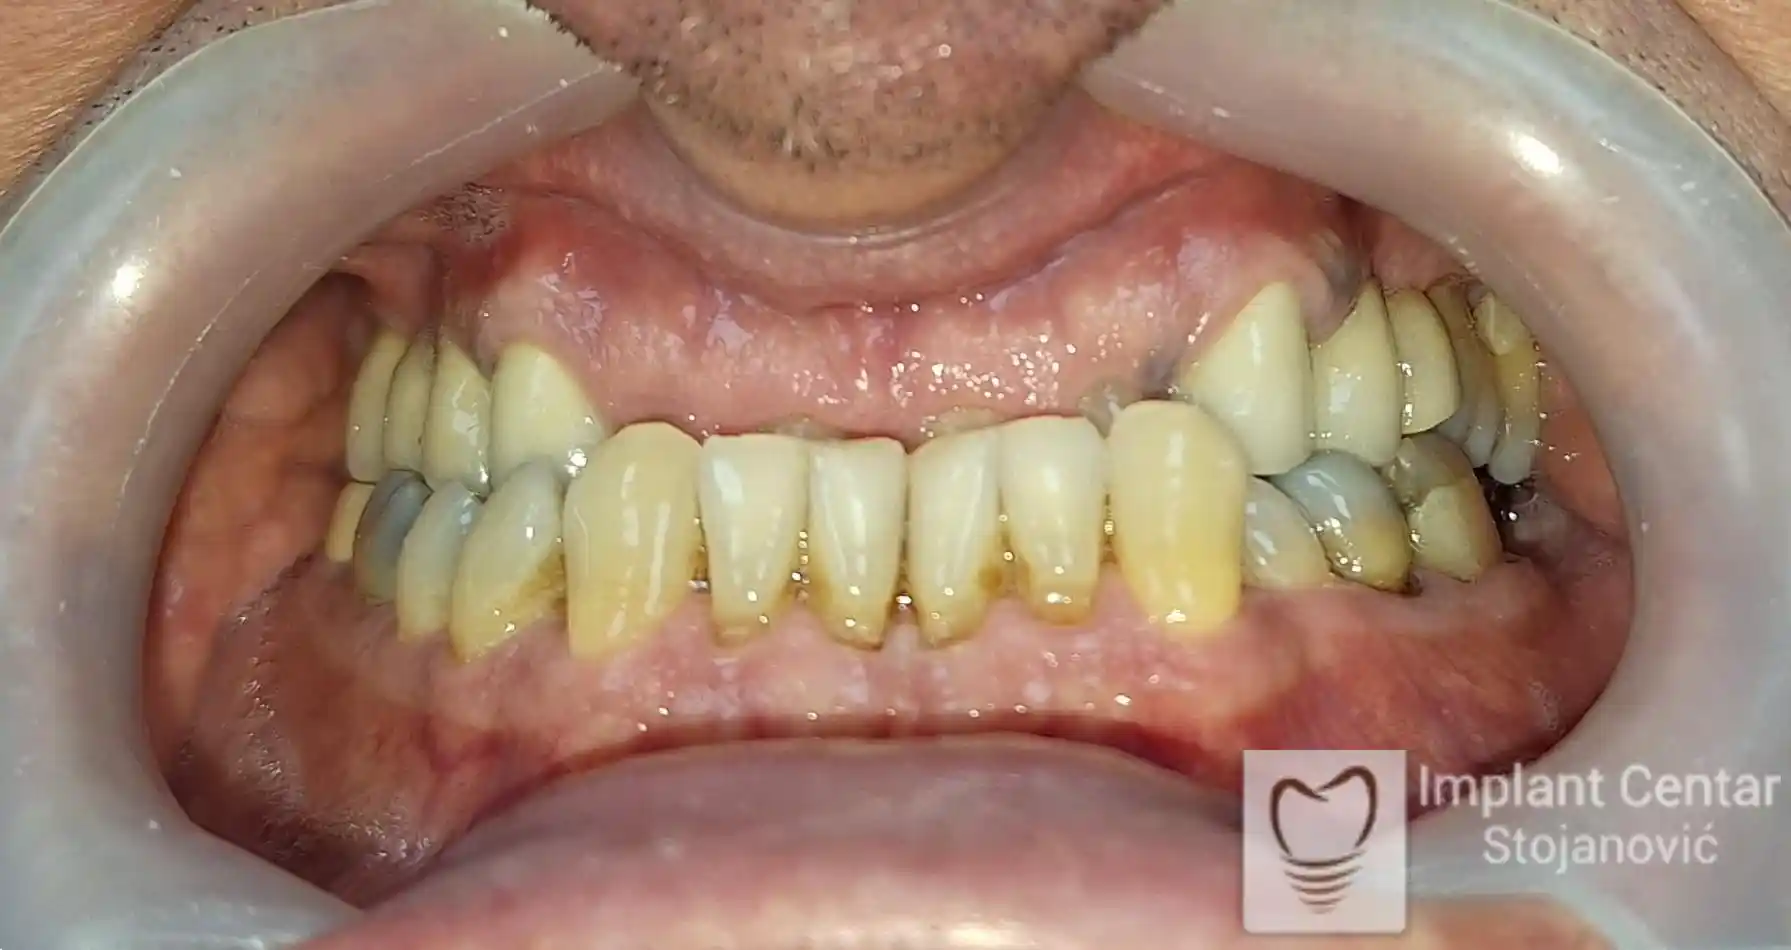

Na slikama 1, 2, 3 , 4  i  5 prikazan je izgled pacijenta pre početka terapije. Nakon detaljne kliničke i radiološke analize, doneta je odluka o vađenju zuba loše biološke vrednosti, dok su bezuba polja sanirana ugradnjom dentalnih implantata.

Po završetku perioda integracije, izrađeni su definitivni cirkonijum-keramički mostovi, čime je postignuta potpuna rekonstrukcija zagriza, kao i značajno poboljšanje estetike i oralne funkcije (slika 12, 13, 14 i 15).